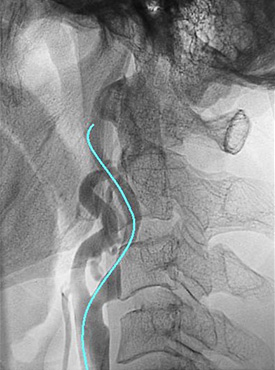

無症候性の右内頸動脈起始部高度狭窄例です。

狭窄部に潰瘍形成を伴う90%狭窄を認めます(黄色矢印)。

動脈が非常に細くなっています。細くなっている部位を風船を用いて拡げます。

再び細くならないようステントを挿入します。